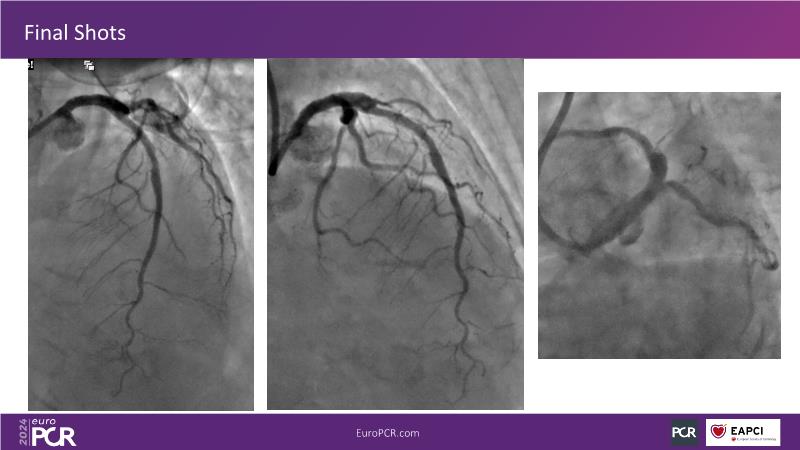

From innovation to reality: the impact of Cre8 EVO technology on complex PCI

This session is a good opportunity to delve into the contemporary technical and clinical complexities surrounding complex PCIs in challenging patient cases. Explore the necessary tools and treatment strategies to enhance peri-procedural and long-term clinical outcomes, and follow discussions on the unique technologies of Cre8 EVO in complex PCI scenarios.